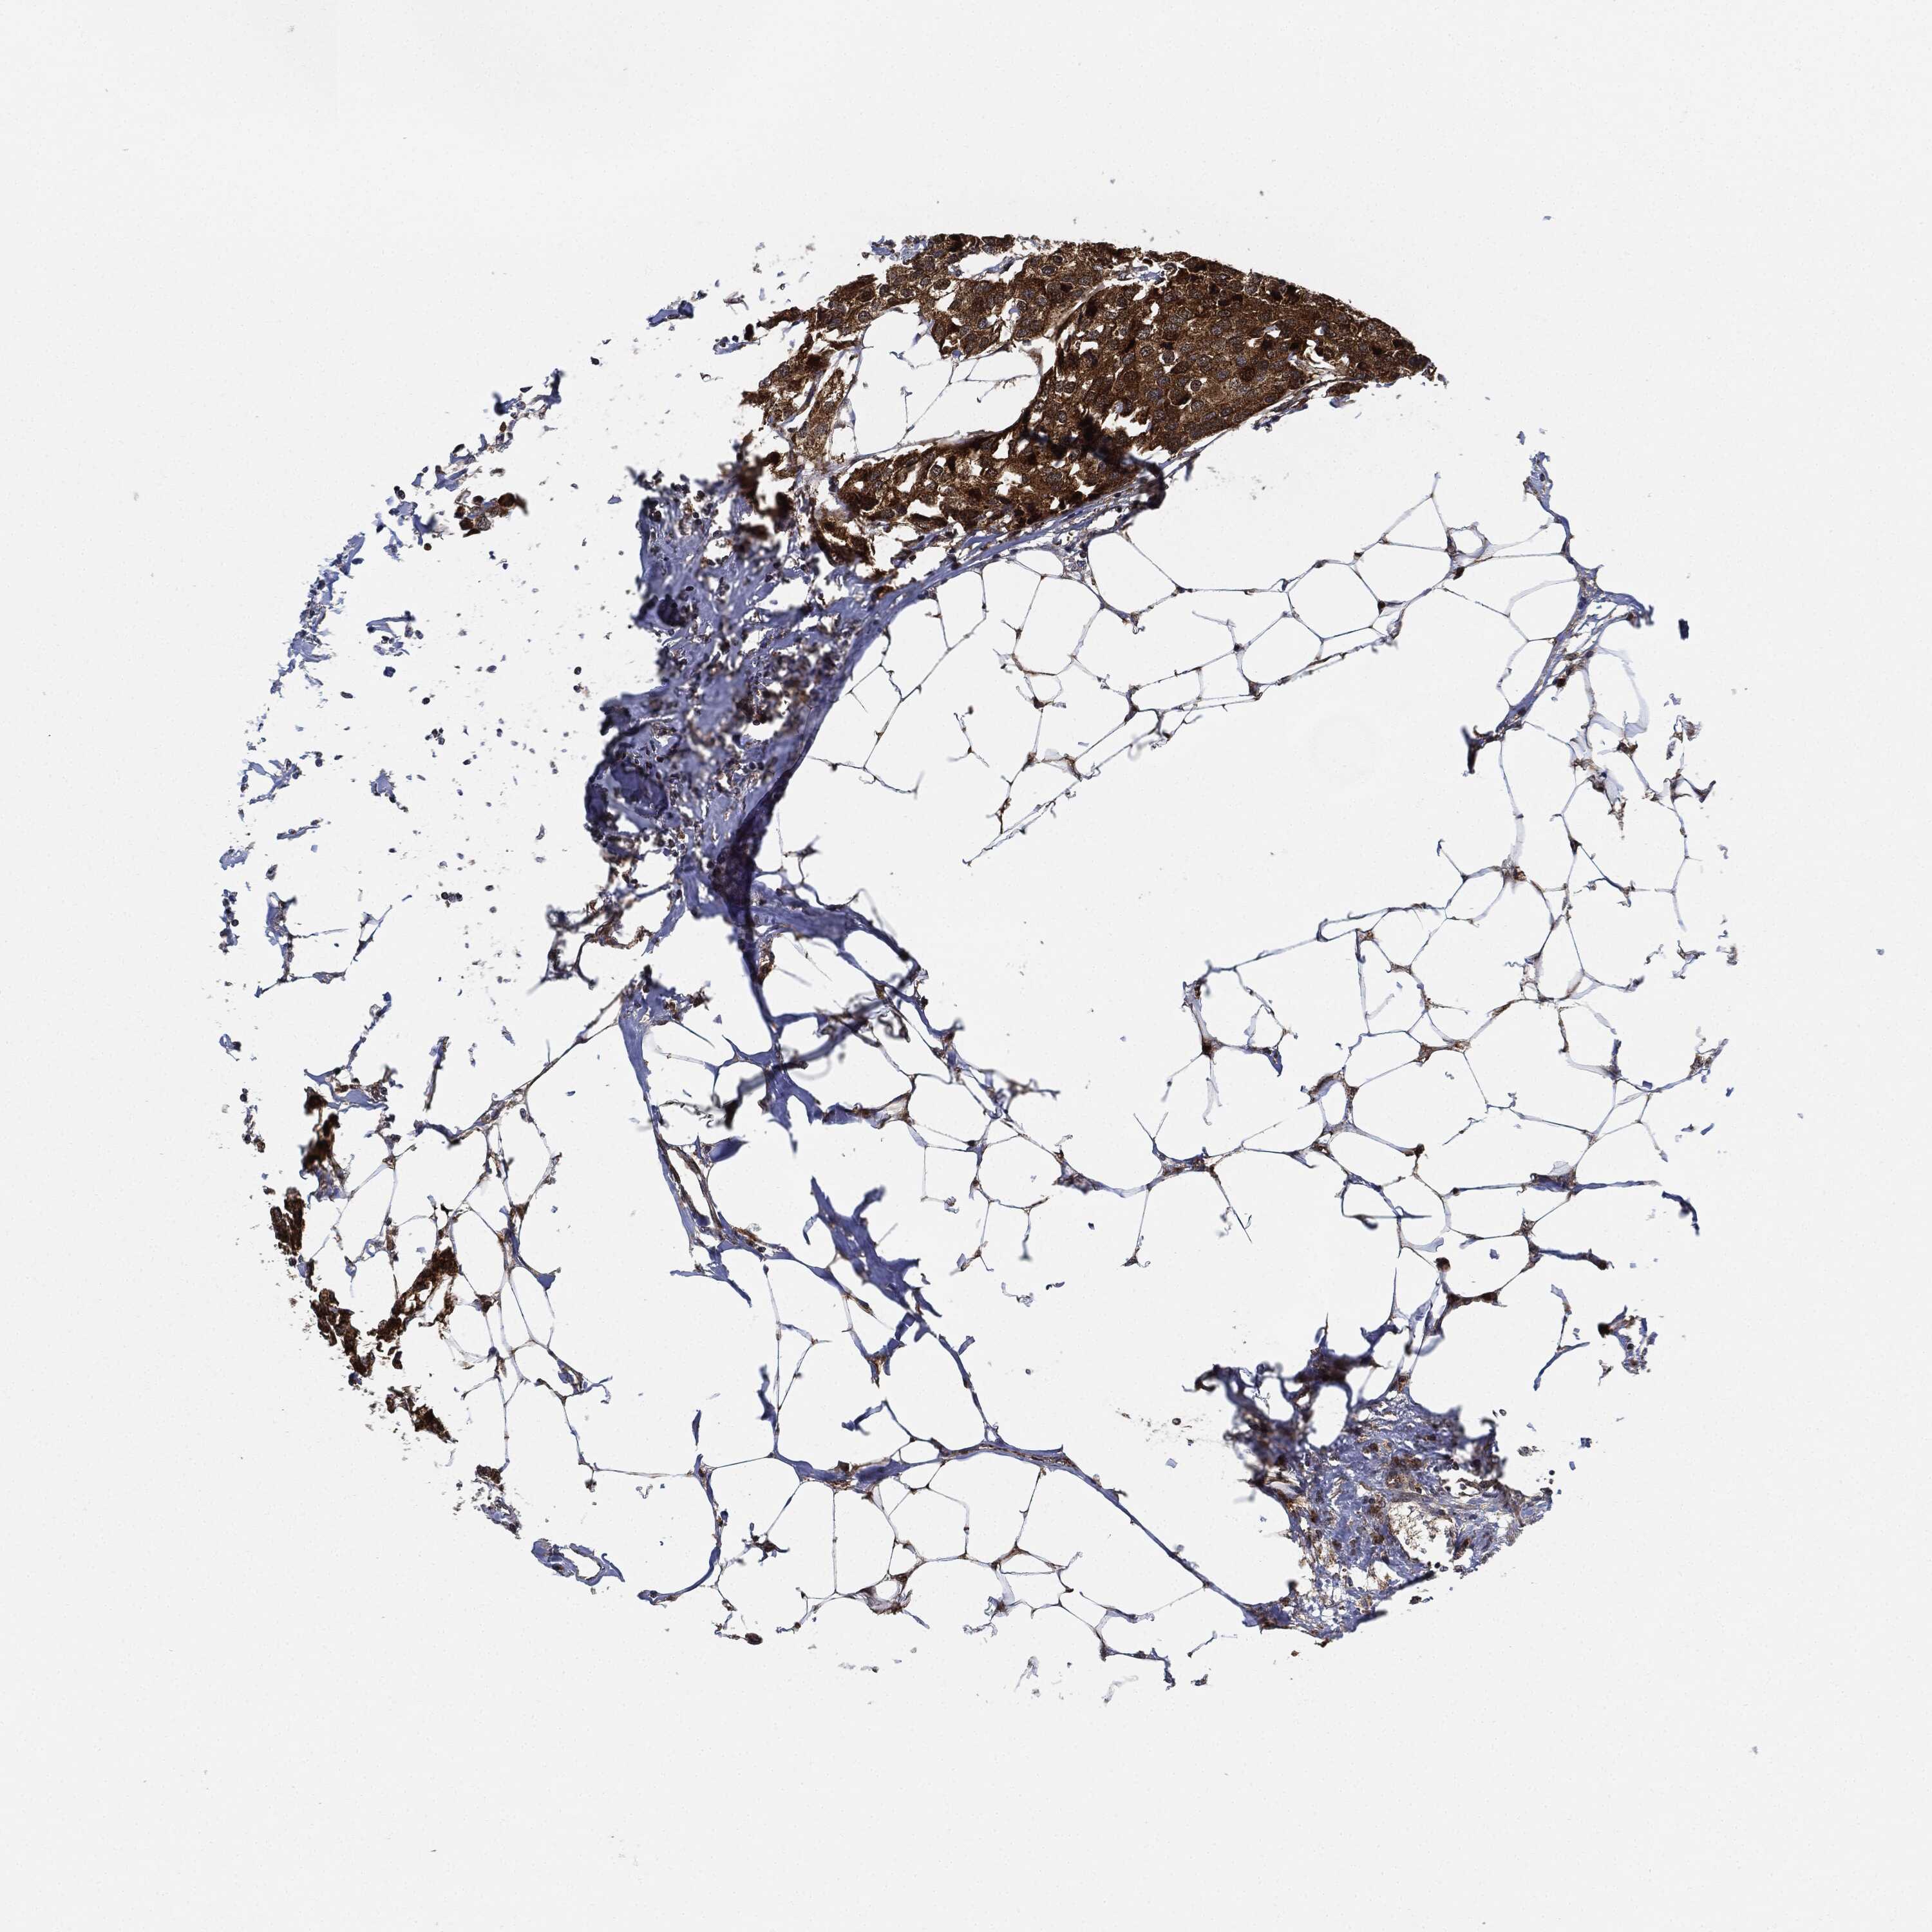

BRCA TCGA BRCA VALIDATION PROTEIN EXPRESSION

ANTIBODIES

AND

VALIDATION